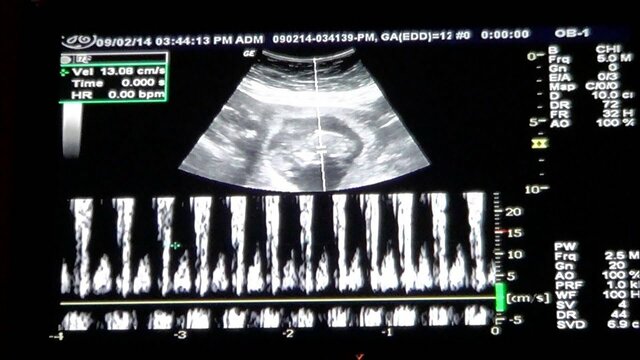

Between 12 to 14 weeks the mother will begin to hear the baby's heartbeat with a doppler ultrasound